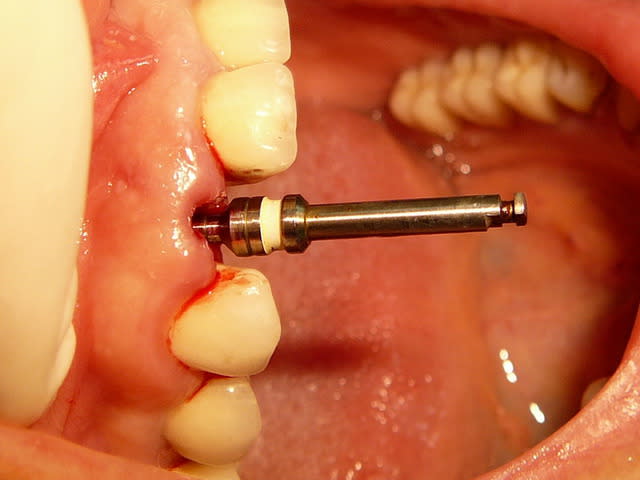

Un pilier de cicatrisation customisé ou personnalisé c'est une vis de ciatrisation individualisée : elle peut être faite de plusieurs facons par exemple à partir de ton porte implant que tu modifies par apport successif de composite.

Ca ressemble à cela :